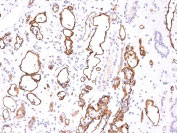

Formalin-fixed, paraffin-embedded human Kidney Transplant stained with Complement 4d Monoclonal Antibody (C4D204).